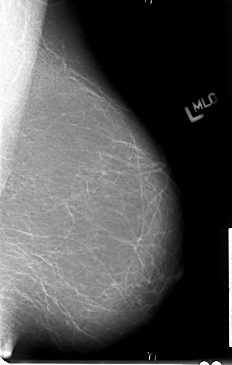

B_3022_1.LEFT_MLO

LEFT_MLO LINES 4736 PIXELS_PER_LINE 3016 BITS_PER_PIXEL 12 RESOLUTION 50 NON_OVERLAY